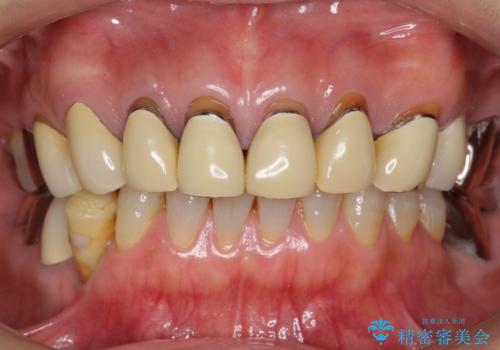

- 前歯のセラミック治療から4年半経過した患者様です。

4年ぶりに来院して下さいました。

治療した上の前歯6本は全く問題なく、「獅子舞みたいだった前歯を綺麗にして下さってありがとうございました!」と再度お礼を言って下さいました。

4年半前のクラウン装着時と変わらず、まるで天然歯のように自然に見えました。

患者様の良好なセルフケアと精密な適合の良いクラウンにより、歯肉の腫脹や退縮も認められませんでした。